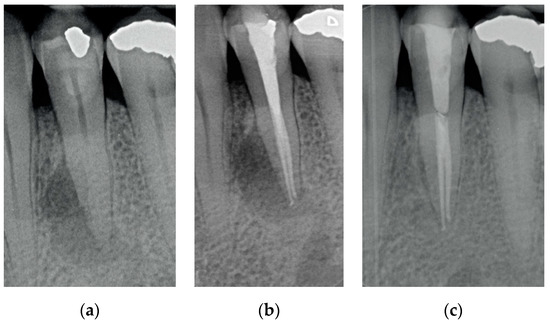

Results showed that 92.61% of ETT did not have any complications up to 18 years (Figure 1, Figure 2 and Figure 3).

Regarding the quality of root filling, 264 teeth (88.59%) showed good filling (Figure 1, Figure 2 and Figure 3) (gutta-percha at the radiologic apex), 22 roots (7.38%) short filling (shorter than 1 mm from the radiographic apex), and 12 (4.03%) long filling (longer than 1 mm of the radiographic apex).

Figure 2. (a) A lower bicuspid in need to be endodontically treated because of necrosis of the pulp and periapical lesion; (b) The tooth after being endodontically treated. Two canals were found, cleaned and filled; (c) The tooth at 2 years recall. The periapical lesion completely disappeared.

The numbers of failures due to tooth fractures, endodontic, periodontal, or prosthodontic reasons, were limited to 22 of 298 ETT. Of the recorded failures, 14 were reported as repairable; eight were catastrophic failures and, consequently, needed root extraction. The success rate was around 92% (Figure 1, Figure 2 and Figure 3), the survival rate around 4.69%, and only less than 2.69% were irreversible failures. The success and survival rates of this clinical study were a little higher than several others [36,37,38]. Another important aspect related to the failure was the fact that irreversible failures mainly took over in the first two years and within the first 5 years, when cumulated as reversible and irreversible failures. It can be speculated that “biological” complications can come out rather quickly, and periodontal and prosthodontic complications in a longer time, but after 5 years of clinical service, it can be expected that an ETT can stay in clinical service for many more years.